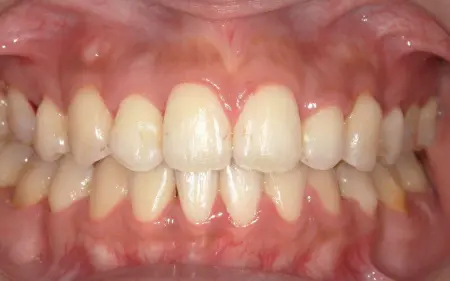

2025.11.0920代女性 マルチブラケット装置やヘッドギアを併用した矯正治療で出っ歯を改善した症例